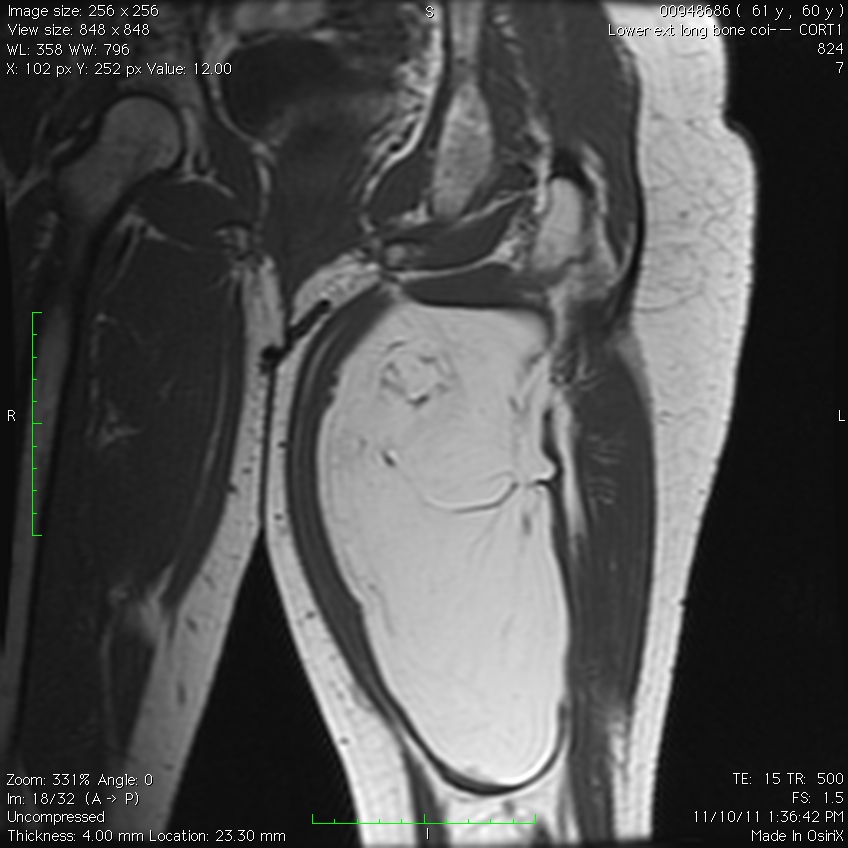

MRI

• Follows the signal characteristics of subcutaneous fat on all sequences

• T1: High Signal

• T2: Intermediate Signal; Low Signal with Fat Suppression

• Minimal or No enhancement with gadolinium

Fig. 1A, 1B, 1C, 2A, 2B, 2C: MRI of a lipoma: T1- weighted images shows an homogeneous mass in the posterior compartment of the thigh with high signal, saturates on fat saturated sequences with no or minimal enhancement. On T2-weighted images demonstrate an intermediate signal on FSE T2, saturates (becomes dark) on fat saturated sequences.